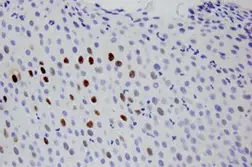

Consiste na detecção de seqüências específicas de DNA em cortes de tecido. utilizando sondas (seqüência de ácido nucleico específico) marcada com biotina. A biotina é detectada por um complexo enzimático e visualizada por uma reação colorimétrica através de um substrato. O sinal da Hibridização do DNA viral é visualizado precisamente no núcleo das células infectadas. Utilizamos o sistema automatizado BONDMAX DA LEICA BIOSYSTEMS.

A positividade do exame permite o diagnóstico específico da infecção pelo HPV em lesões genitais benignas, pré-cancerosas ou malignas e, eventualmente, em lesões extragenitais. A grande vantagem da hibridação in situ é a possibilidade de correlacionar os achados com os aspectos morfológicos/histológicos das lesões sem que haja necessidade de amostra fixada em meios especiais, o que permite a análise de biópsias ou peças cirúrgicas fixadas em formol a 10%, material congelado, cultura de células, preparados citológicos e blocos de parafina. A hibridação in situ é o método de escolha para a detecção nos tecidos, de seqüências específicas dos ácidos nucléicos do genoma do HPV presente nas células-alvo e para a associação dos achados com lesões histológicas. As sondas atualmente disponíveis para a realização do exame discriminam grupos de vírus com potencial de alto risco para oncogênese (tipos 16, 18, 31, 33, 35, 39, 45, 51, 52, 56, 58, 59 e 68) dos subtipos não comumente relacionados com o desenvolvimento de neoplasias malignas, mais associados a lesões condilomatosas (tipos 6-11). A pesquisa positiva confirma a presença do HPV na amostra, mas a negativa não afasta completamente a possibilidade de um dos outros tipos de HPV não compreendidos pelas sondas estar presente. Dessa forma, há necessidade de avaliação dos resultados anatomopatológicos para definir a melhor opção de conduta de seguimento e tratamento clínico, quando indicado.